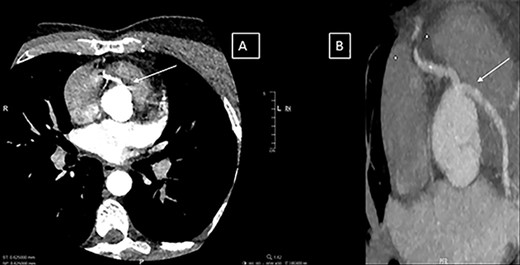

A previously fit and healthy 47-year-old man was admitted to his local hospital with delayed infero-lateral ST segment elevation myocardial infarction (STEMI). His surgical history was significant for correction of left forearm deformity since childhood. He had persistent left forearm contracture with significant atrophy in in left arm and left leg. He was treated medically at the time of presentation and transferred to our center for coronary angiography, which showed significant triple vessel disease arising from single right coronary ostium (Fig. 1). Transthoracic echocardiography showed ejection fraction of 40% with hypokinesia of inferior and lateral walls and trivial mitral valve regurgitation with no associated congenital defects. Computed tomography (CT) of the heart (Fig. 2) showed both left main and right coronary arteries arising from one single ostium in the anterior coronary sinus. Left main stem was seen passing between aorta and right ventricular outflow tract in sub pulmonic course. Left anterior descending artery (LAD) was short and had significant stenosis in its ostium. Magnetic resonance imaging (MRI) heart showed no evidence of any cardiovascular congenital anomalies with situs solitus and levocardia with normal arterial trunk connection. As his coronary anatomy was unsuitable for stent insertions, he was referred for coronary artery bypass graft (CABG) surgery. Patient underwent CABG through median sternotomy with left internal mammary artery anastomosed to LAD, reverse saphenous vein graft anastomosed to obtuse marginal and reverse saphenous vein graft anastomosed to posterior descending artery. LAD was deep intra myocardial. Procedure was performed with cardiopulmonary bypass (CPB) and cardioplegic arrest. Patient was weaned from CPB with minimum doses of norepinephrine and was extubated 12 hours post operatively. He was discharged home uneventfully on fifth postoperative day with no complications. On follow-up at 12 months, he remained well with no symptoms.

(A and B) Computerized tomography images showing the single coronary artery ostium and pathway of the abnormal vessel.